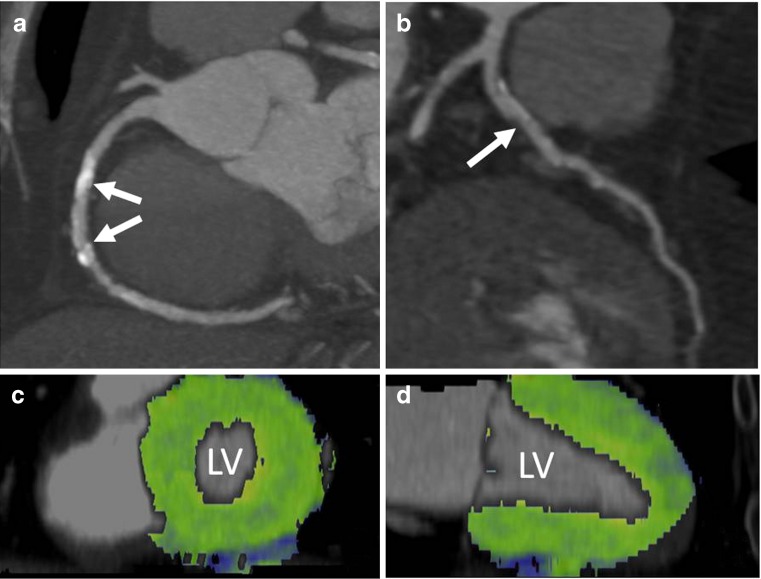

Fig. 5.

A 71-year-old male patient who presented with stable chest pain syndrome and a history of cigarette smoking, hyperlipidaemia and hypertension. His right (a) and left anterior descending coronary arteries (b) demonstrate the presence of calcified and non-calcified plaque in all proximal vessel segments. The middle segment of the RCA has extensive calcification (arrows). Owing to limited evaluability of the coronary lumen, the presence of significant coronary artery stenosis could not be ruled out. As part of a research protocol, the subject underwent dynamic adenosine-mediated stress myocardial perfusion imaging (100 kV, 175 mAs/rot) over a period of 30 s. Fusion images of the left ventricle (LV) in long axis (c) and short axis (d) demonstrate homogeneous myocardial blood flow without any evidence of stress-induced myocardial hypoperfusion. The measured myocardial blood flow was approximately 125 ml/min/100 g